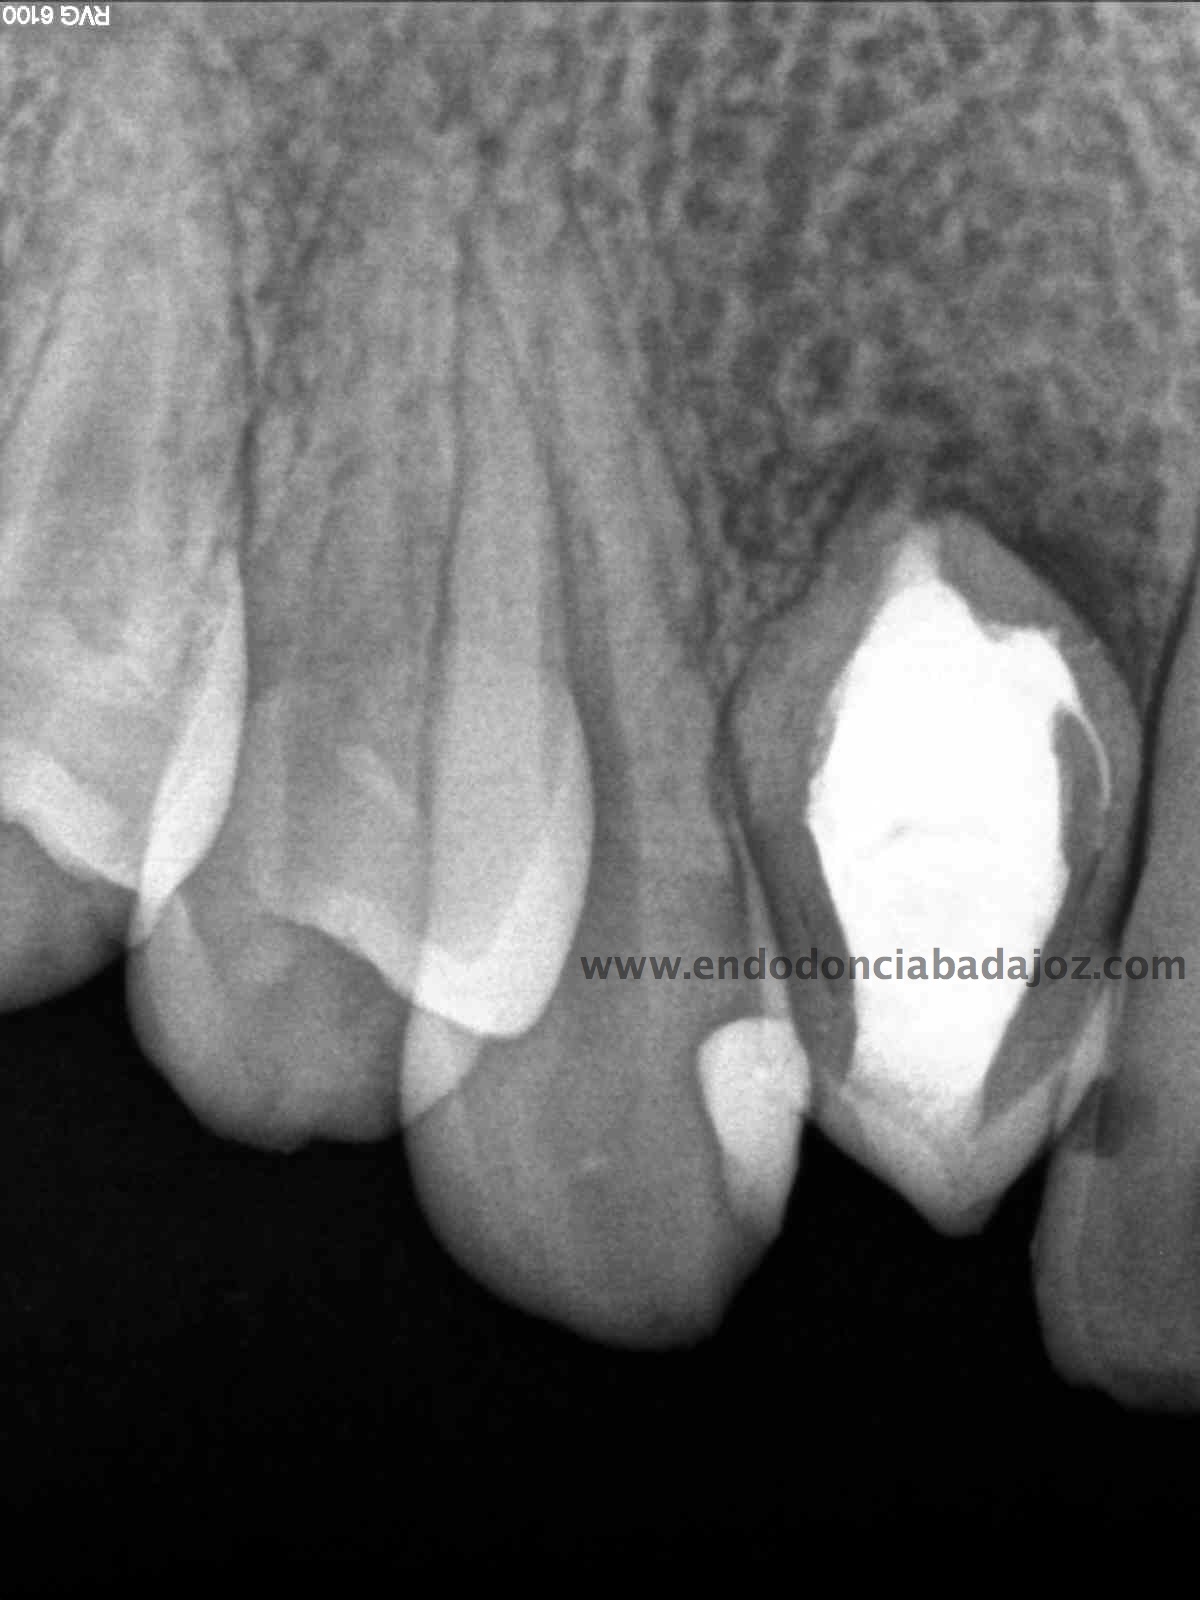

Nuestro caso, se trataba de esta pieza con necrosis pulpar con afectación periapical que presentaba una vía de drenaje (fístula). Esta radiografía muestra el camino de la fístula a la lesión apical.

Se planteó el caso con una apertura del mismo y tratamiento de todo el conducto con puntas de ultrasonido desbridando las paredes e intentando no eliminar demasiado tejido dentinario. El primer paso sería conseguir una permeabilización del conducto:

Como defensor del H de Ca ,en ciertas ocasiones, en este caso colocamos el mismo. En la siguiente cita, después de tallar el conducto, colocamos un sellado apical con cemento M.T.A. de varios milímetros y obturando con gutapercha inyectada con la pistola Obtura II.